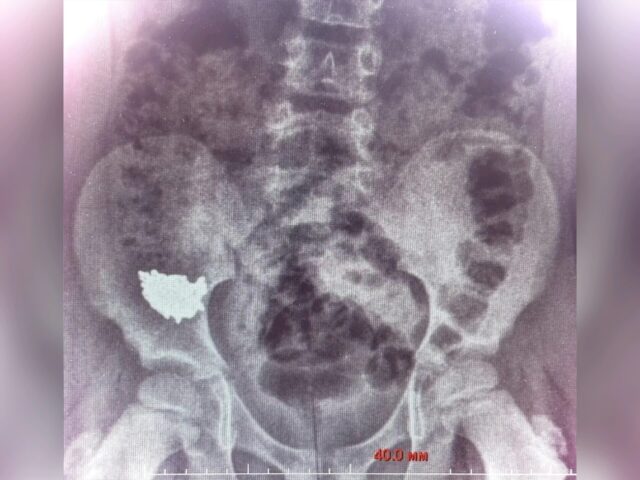

Сначала малыша госпитализировали, назначили наблюдение и консервативное лечение. Но контрольные снимки на третьи и четвёртые сутки показали, что инородное тело застряло в правой подвздошной области и напрочь отказалось двигаться по ЖКТ. Дальше ждать было нельзя — высок риск воспаления или образования отверстия.

Под общим наркозом хирурги сначала попробовали менее травматичный метод: сделали колоноскопию, надеясь достать украшение эндоскопически. Но в толстой кишке цепочки не оказалось. Пришлось идти дальше — провели ревизию брюшной полости. Цепочка обнаружилась внутри аппендикса. Её аккуратно извлекли, а сам отросток удалили — провели стандартную аппендэктомию.